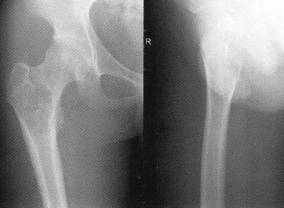

图1右股骨内生软骨瘤

A.X线股骨正侧位片示右股骨上段有一卵圆形低密度透亮区,呈中心性,边缘清晰,病灶周围见一薄层高密度硬化环;其内见斑点状高密度钙化,邻近骨皮质完整,未见骨皮质破坏和膨胀性改变;